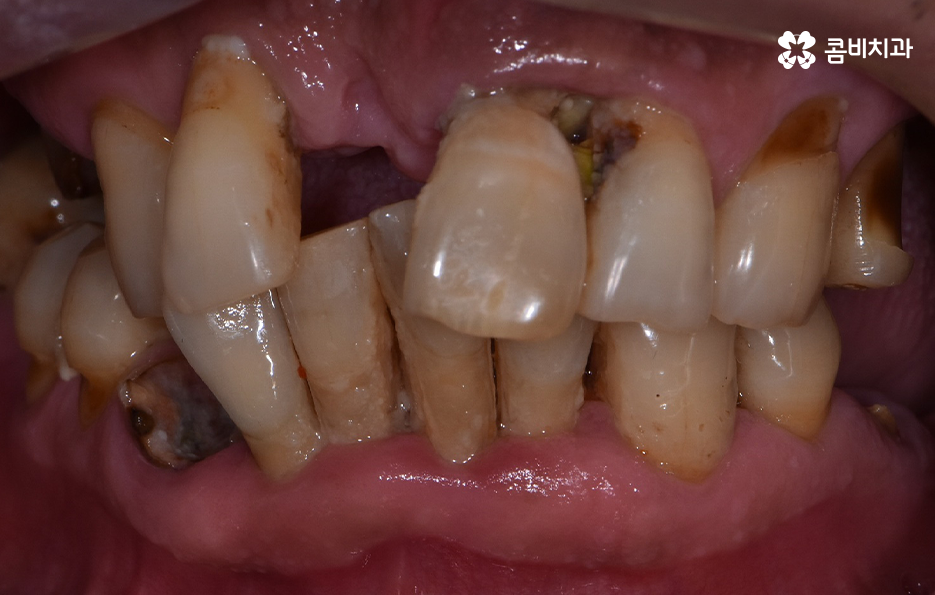

치주염으로 인해 잇몸이 내려앉고 치아의 뿌리가 흔들려서 발치했어요

위 환자분의 엑스레이 사진을 보면 치아의 뿌리 부분에 가깝게 잇몸이 내려앉은 것을 볼 수 있는데 치아의 구조에서 뿌리쪽은 법랑질이 없기 때문에 잇몸이 내려앉고 잇몸 뼈가 치주염으로 녹게 되면 치아가 너무 아파서 식사를 하기에도 어렵고 물 한잔만 마셔도 이가 시릴 정도로 일상에 지장을 느끼실 수 있어요

고령의 환자분들의 경우에는 잇몸 뼈의 상태 뿐 아니라 전신질환, 회복력을 함께 고려해야 하기 때문에 치료 계획에 있어서 보다 섬세하게 체크해야 하며 환자분의 잇몸 뼈 상태와 전신건강 그리고 경제적인 상황 등을 고려할 때 전체임플란트를 하게 되는 경우도 있지만 위 환자분의 사례처럼 임플란트를 최소한으로 식립하여 임플란트의 보철물을 연결하여 치아의 기능을 회복하는 경우도 있는데요

치주염 발치 해야 하는 상황으로 대부분의 치아를 잃게 된 경우이거나 임플란트를 여러개 식립하기에는 경제적 부담이 크다면 임플란트의 식립 개수는 최소화하고 보철물을 틀니처럼 사용하시는 경우도 있는데요. 앞니의 경우 식사 시에 치아에 받는 압력이 어금니에 비해 적은 편이지만 어금니의 경우 충분한 저작력을 유지하기 위해서는 충분한 두께의 잇몸 뼈에 임플란트를 식립해야 하기 때문에 잇몸 건강의 중요성에 대해 꼭 늦지 않게 신경써주시길 바라고 있어요